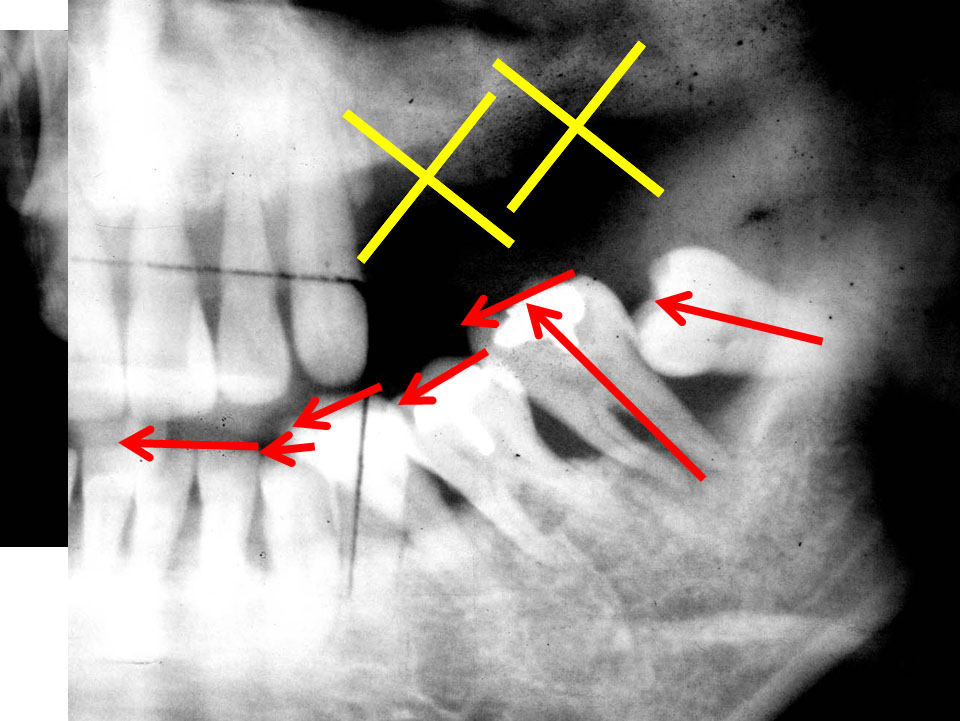

さあ、ではこのレントゲン写真は何が起こっているんでしょうか?

右下奥に斜めに生えているのが親知らずです。親しらずは矢印の方向にエイッエイッと押し続けています。

親しらずが押す力により隣の歯が上から下に突き上げてられています。

歯というのは頭でっかちの形態ですので歯の頭部分に引っかかって上に押し上げられるんですね。

噛み合う上の歯はもう抜けてなくなっているため押し上げられた歯はどんどんどんどんさらに押し上げられます。

上に押し上げられたさらに隣の歯達はドミノ倒しのように横へ横へと倒れ続けます。

この押す力はずっと続きます。わずかな力でも押し続けることにより歯並びはどんどん崩れます。怖いですよね。

さあ、次のレントゲン写真です。赤いのは歯の神経です。

わかりやすく手前の7番目の歯の後ろ側の根と神経血管部分にラインを引いています(本来は右の歯のように神経血管が通っているトンネルの状態ですので、黒い線となって写ります)。

「親知らず」8がお隣の6番目の歯、7番目の歯に対して横にむいてきてるわけですね。

今後どうなると思いますか?神経が圧迫されて痛いのです。

横に倒れていますから、自然に待っていても絶対生えてきませんね。

ほっといても上向きに出てこないですから、生えてきたら抜きましょう、歯茎に隠れてるから抜くのたいへんですから、腫れますからっていって置いておくと、こんな風になってしまうのです。

どうなってしまったか?

わかりますか?

親知らずによって、手前の歯の神経がちょんとブチ切られていますよね。

昔のゲームに「パックマン」ってありましたよね。

そんなイメージでしょうか。食べられてしまっています。

ものすごく痛がりますよね、この患者さんは。

とても痛いと思います。

歯の神経血管は顎の後ろから顎骨の深い部分中を通って歯の根から入っていきます。

ここをちょんと切られるわけですから、とんでもなく痛いのです。

「何とか歯を残してください、親知らずを抜きますから」と患者さんはおっしゃいました。

しかし、すでに7の神経が切れていますから、指が切れて落ちてるわけですから、死んだ人をよみがえらせてって言われても残念ながら手遅れなのです。

無理なのです。

なので、「親知らず」は他の歯に影響が出る前に抜いたほうが良いと私は思っています。